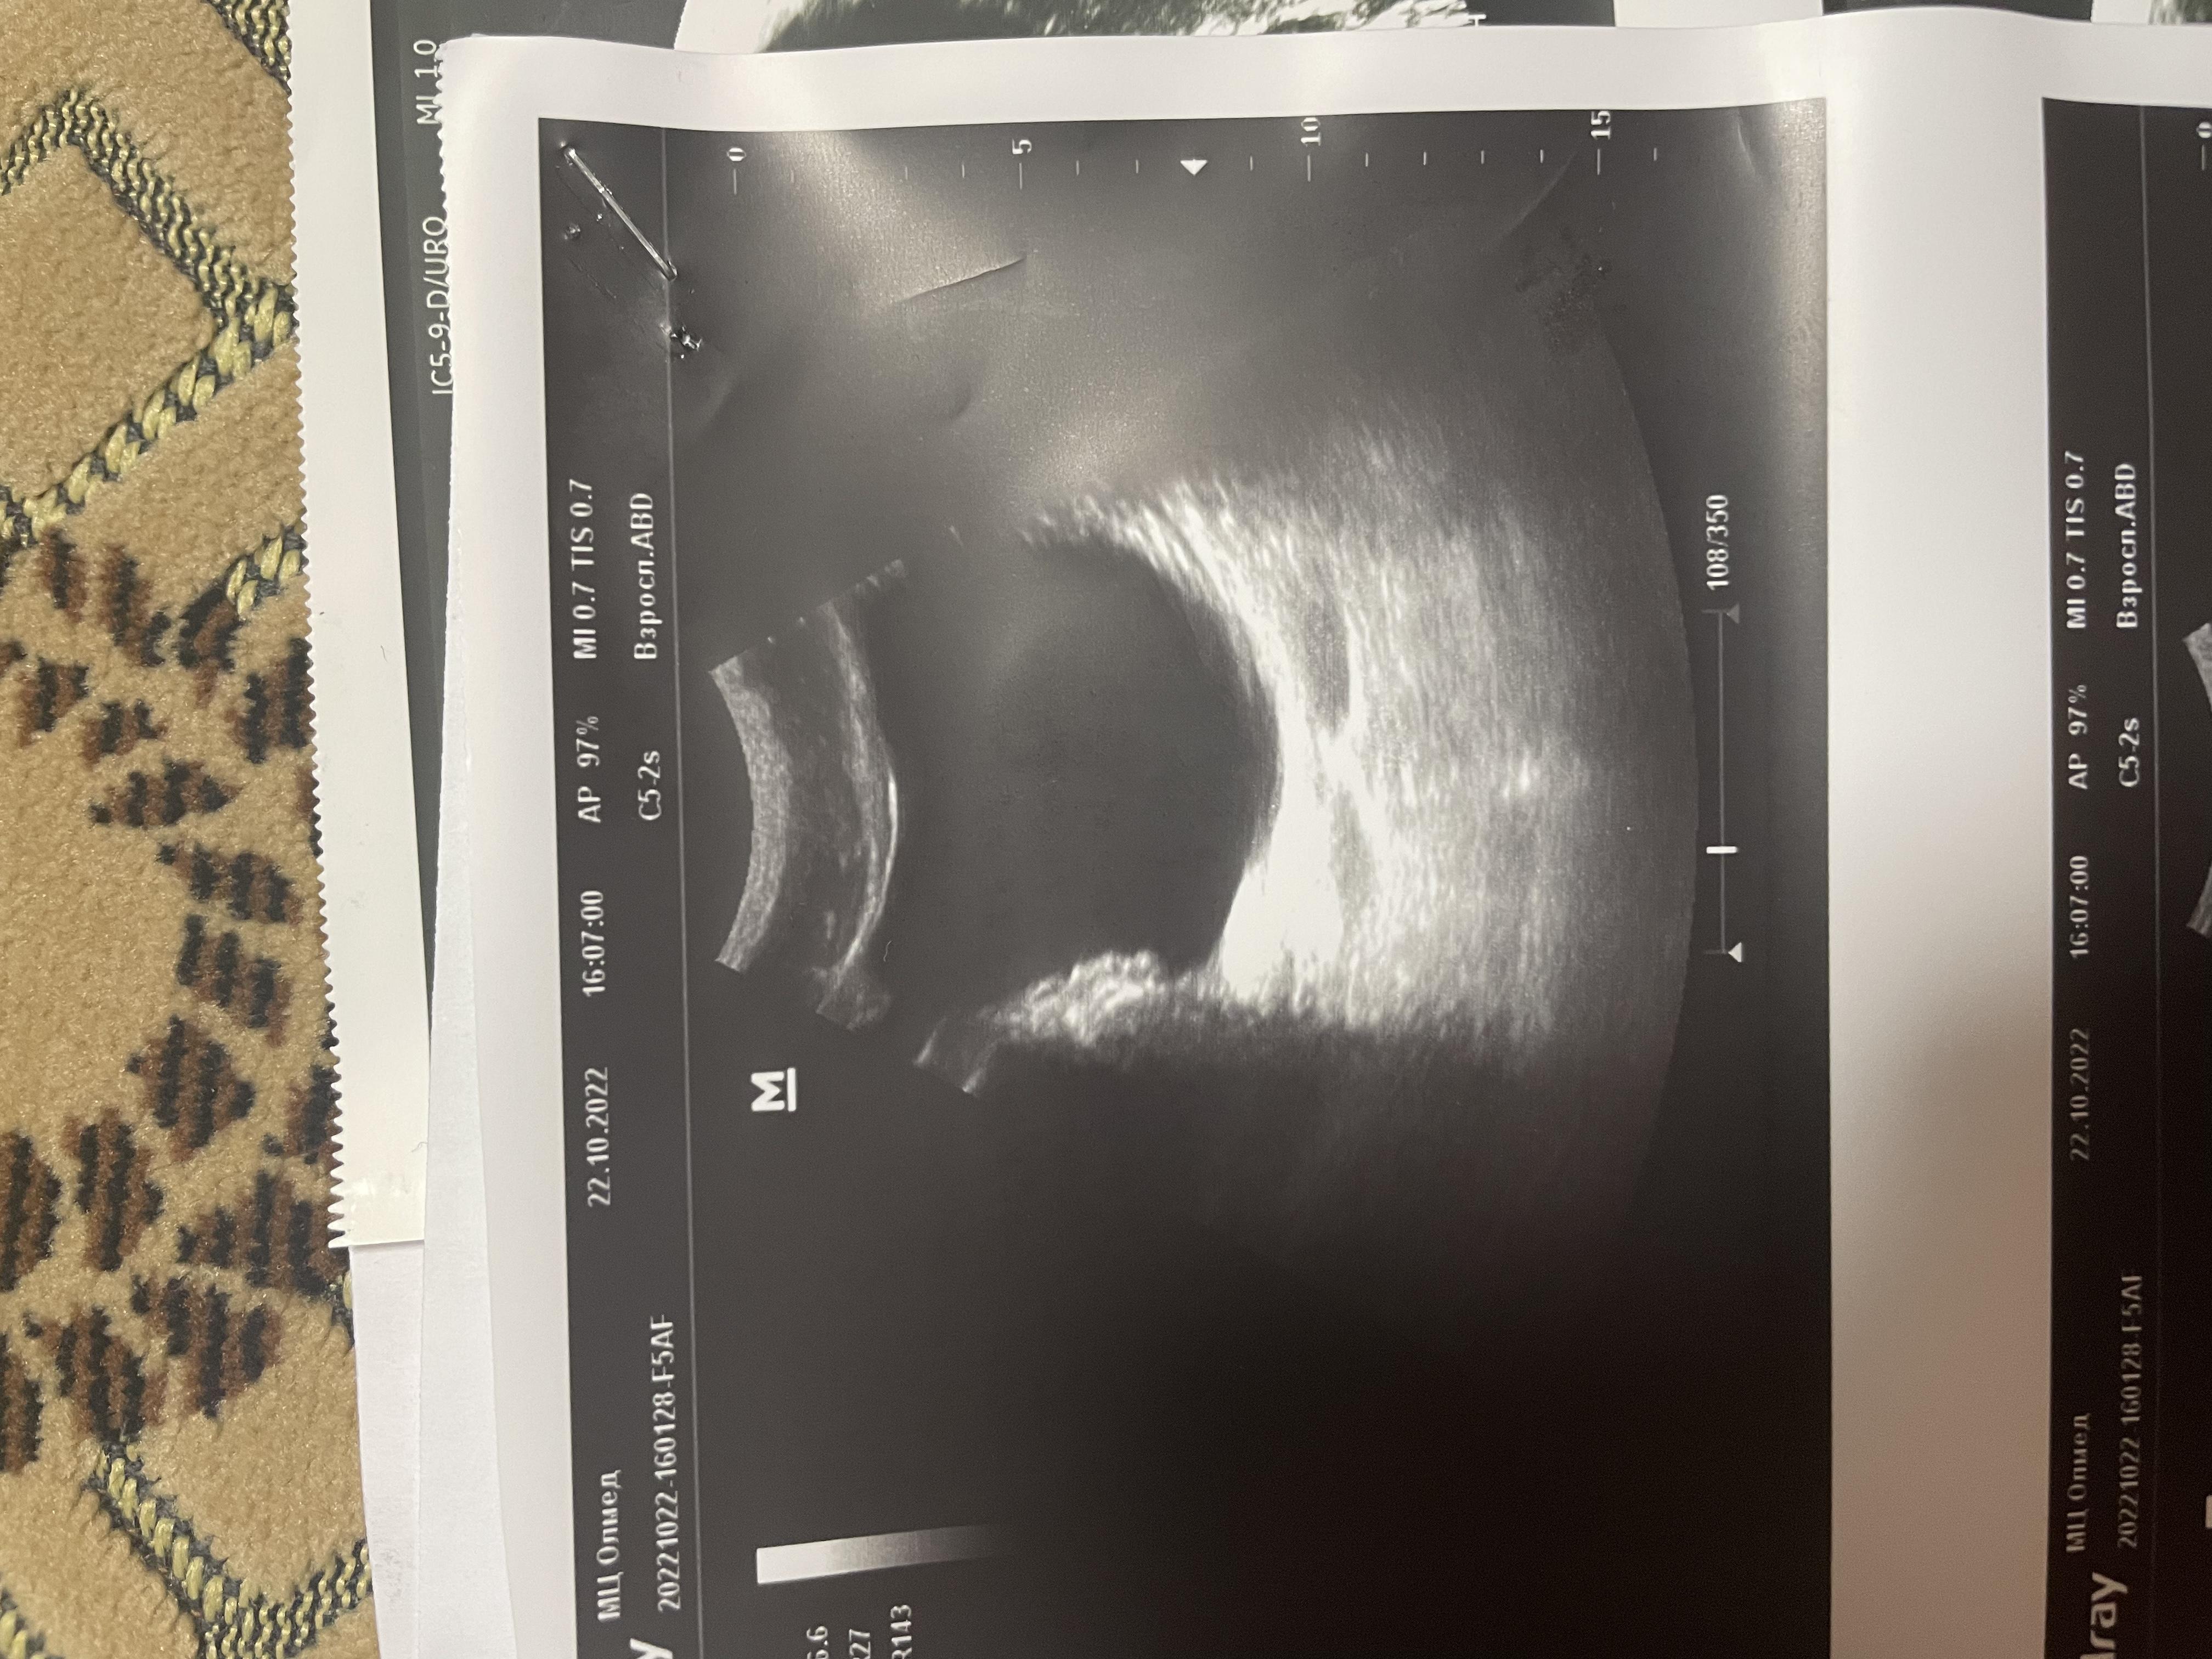

Здравствуйте, болят яички 1.5 года. 6 месяцев режет при мочеиспускании, боли в копчике (начинается с копчика, в течение дня усиливаются, поднимаются выше боли). Может ли это быть из-за мочевого пузыря? Фото прикрепил, там есть образование некое. Бак посев мочи отриц, эр, лейк. в норме, зппп отриц, в секрете простаты клебсиела, кровь в норме, млча в норма. Мрт поясницы делал, невролог сказал, что боли точно не из-за невролгии.

Добрый день! Вам нужно выполнить МРТ малого таза - там будет видно образование в стенке мочевого пузыря (если оно действительно есть). После этого надо обратиться к онкоурологу для интерпретации результатов МРТ и решения вопроса о дальнейшей тактике. Удачи.